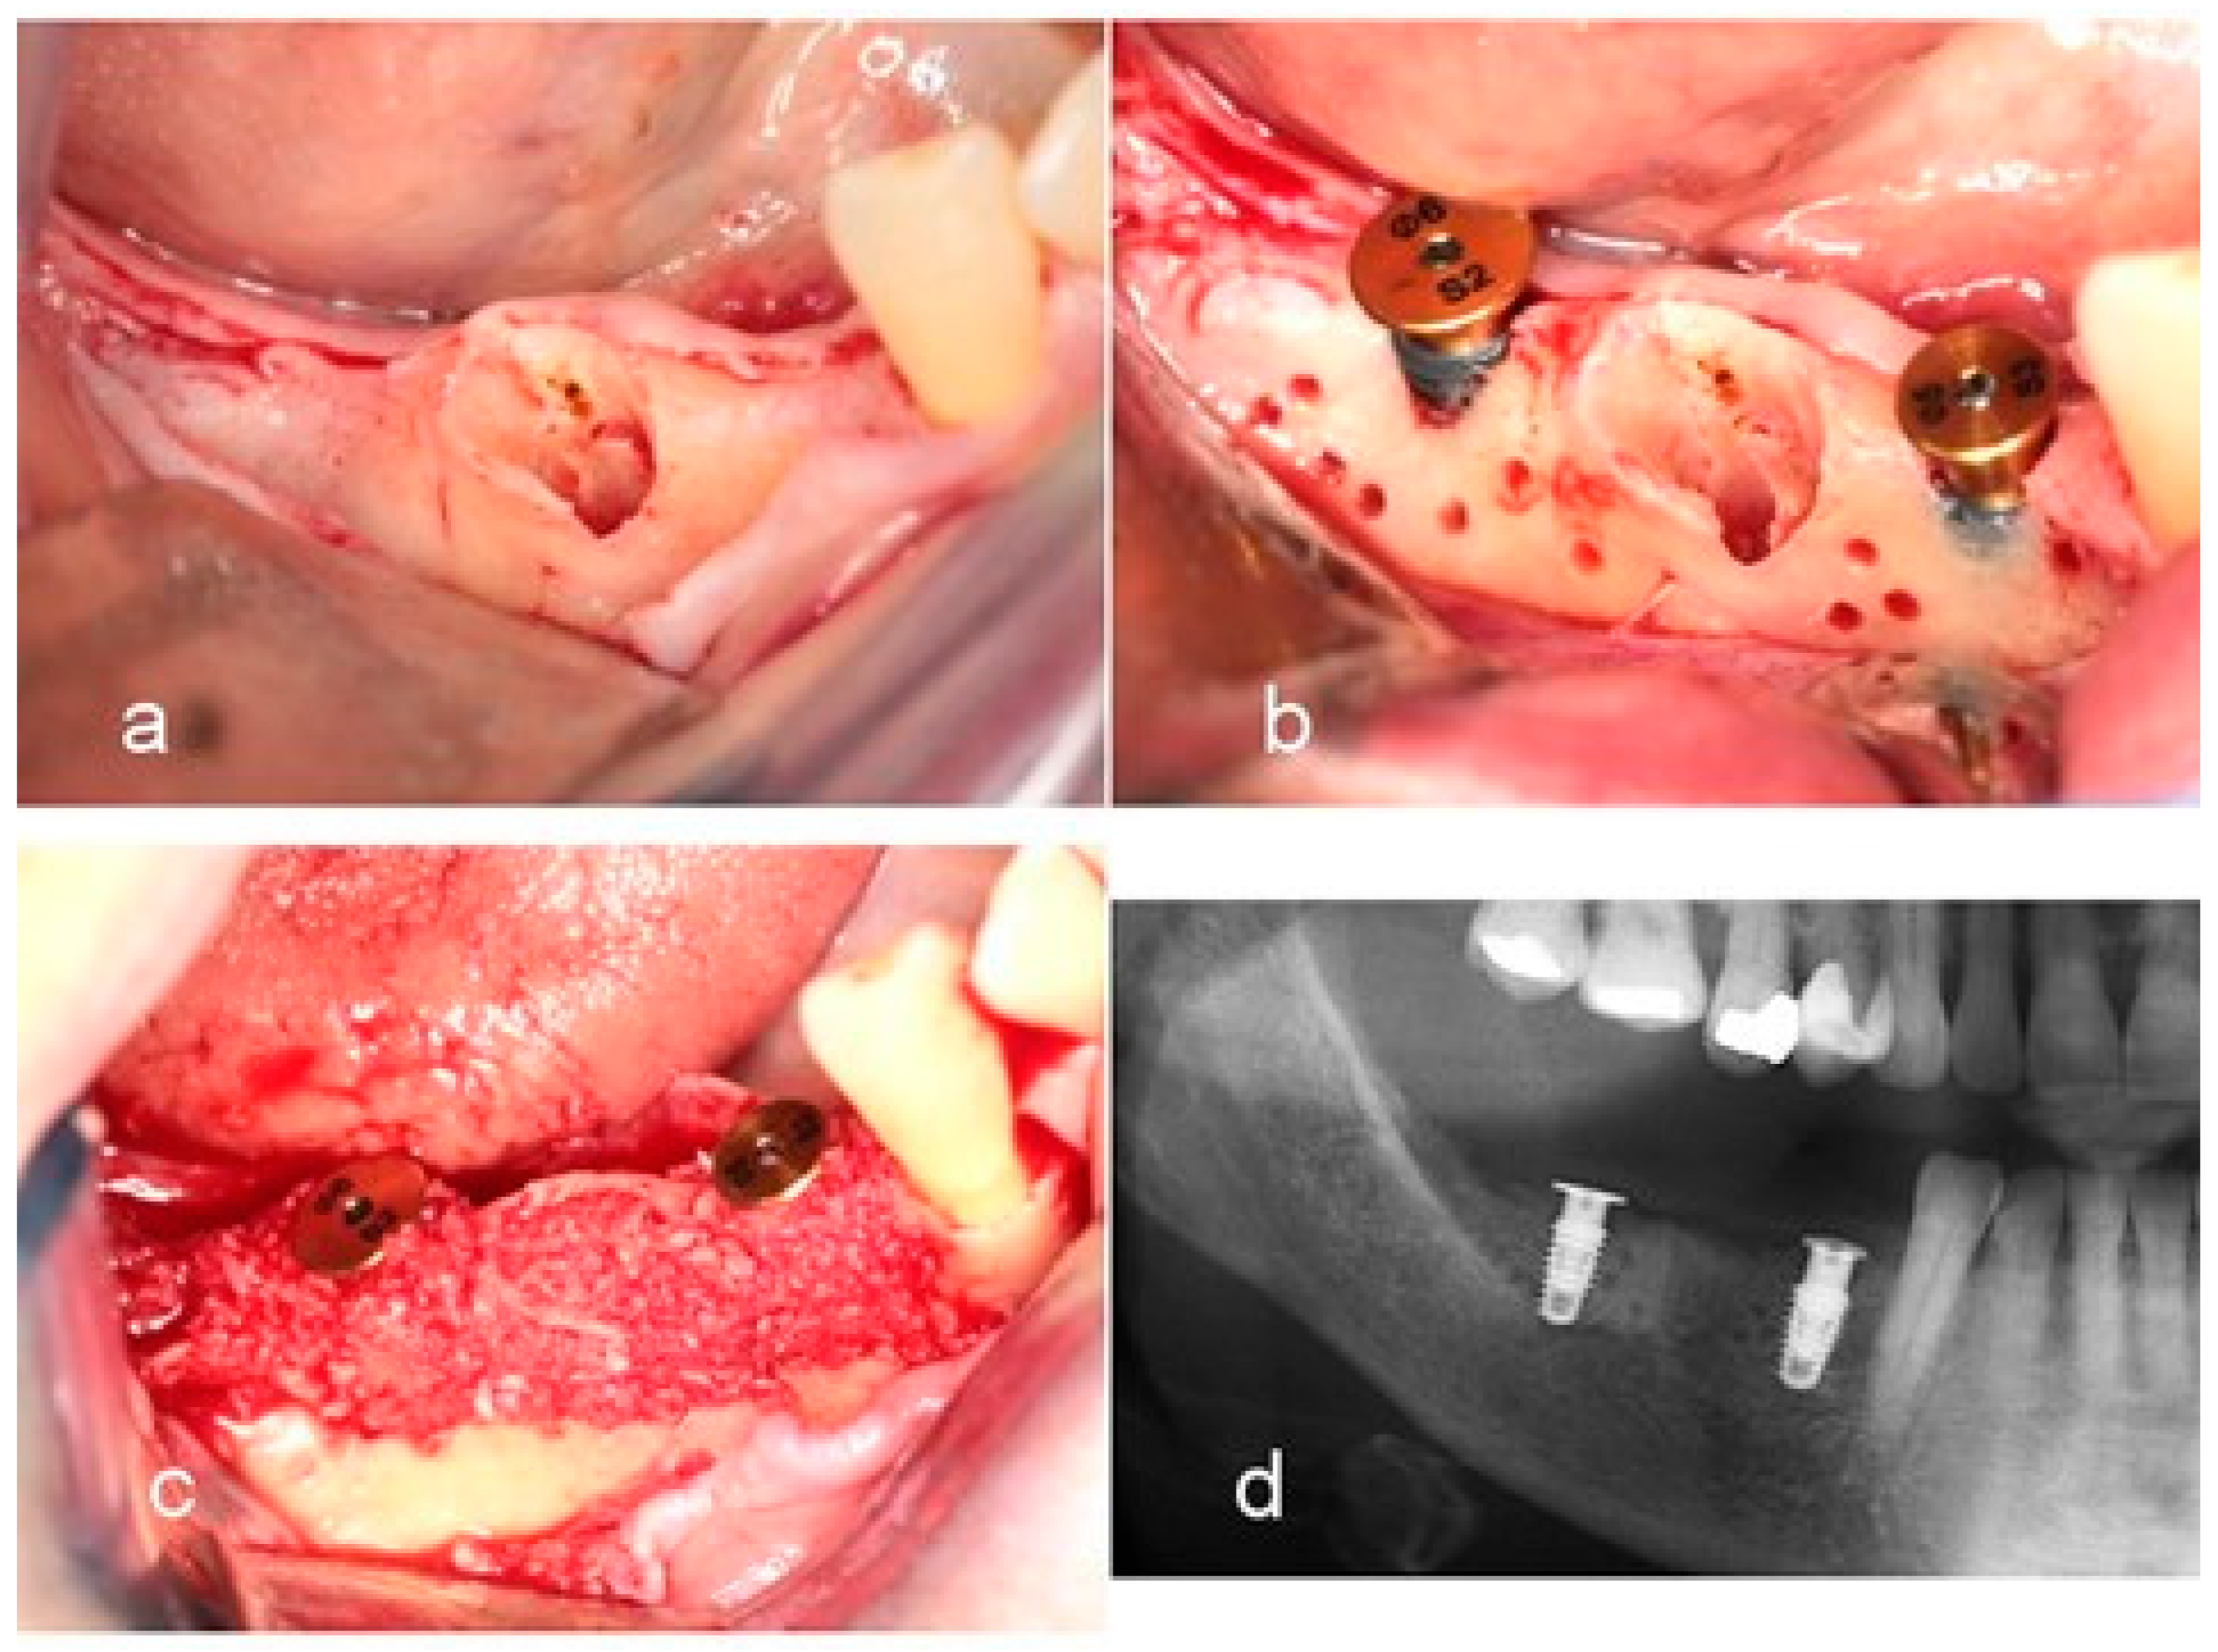

- Woo, R.H.; Kim, H.G.; Kim, G.; Park, W.E.; Sohn, D.S. Simplified 3-dimensional ridge augmentation using a tenting abutment. Adv. Dent. Oral. Health 2020, 12, 185–205. [Google Scholar]

- Sohn, D.S. Reconstruction of three-dimensional alveolar ridge defects utilizing screws and implant abutments for the tent-pole grafting’ techniques. In Essential Techniques of Alveolar Bone Augmentation in Implant Dentistry, 2nd ed.; Tolstunov, L., Ed.; Wiley Blackwell: Hoboken, NJ, USA, 2023; pp. 404–418. [Google Scholar]